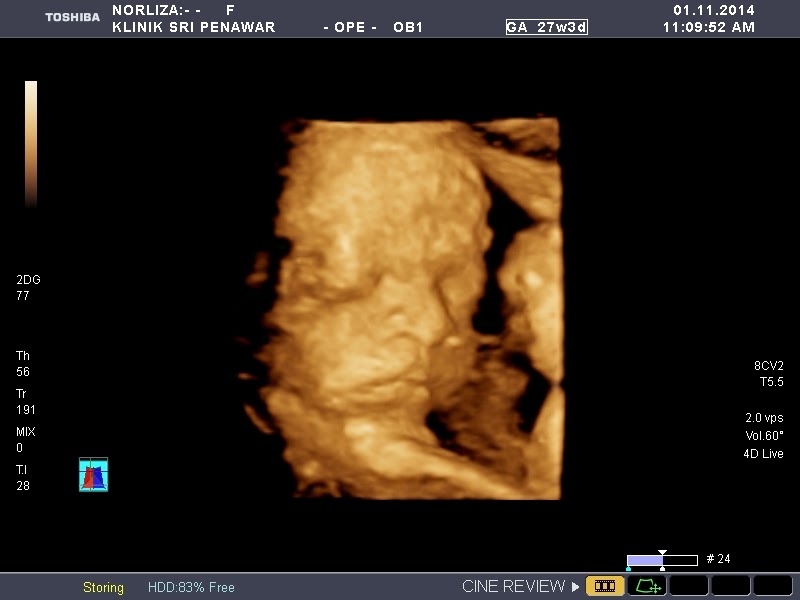

Masa scan 4D tu baby tengah tidur. Dapat la jugak tengok muka baby. Cik Auni pun ada sekali. Mummy excited lebih hehehe. Hidung baby mummy rasa cam hidung ayah. Muka tak tahu la ikut siapa. Baby masam je...tak suka agaknya kena kacau time dia tidur. Saya buat scan 4d ni dekat Klinik Sri Penawar, Kuala Selangor. Kos RM130 dapat gambar & CD. dalam CD tu ada gambar & video sekali. Saya tak tahu tempat lain berapa diorang caj. Masa Cik Auni haritu cuma dapat gambar saje. Tu pun tak clear. Eh masa Cik Auni haritu 3D. Kalau tak silap saya dalam RM150. Untuk 4D ni saya bayar separuh je dalam RM50. Selebihnya saya guna medical.